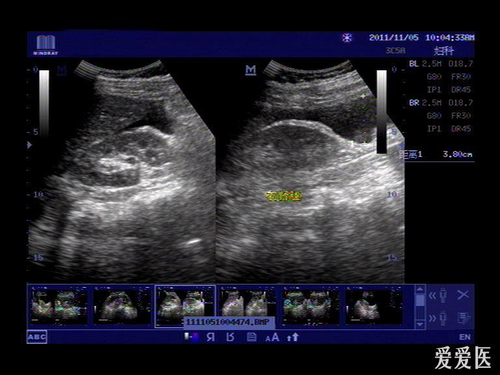

但其实如果是宫外孕的话,一般会在孕35-40天就会有症状的,如腹痛、见红等,因此建议一旦发现异常时,应立刻到医院使用B超检查确认。

宫外孕对于孕妇来说是十分危险的妊娠情况,如果没有引起重视的话,是会威胁孕妇的生命安全的,由于宫外孕没有办法可以在早孕试纸或验孕棒检测出来,同样抽血验孕也不能检测是否宫内妊娠,因此在确定怀孕之后,并且在停经有40天的时候就要进行B超检查确诊。